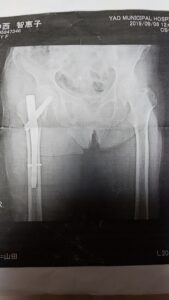

2019/09/25 おはようございます😃 院長の関谷です✨ 祖母が転倒し、骨折しました😅 99歳の誕生日を目前にした日でした。 右の大腿骨の転子間骨折ですかね😅 早く元気になってほしいです✨ そして、白寿のお祝いさせとくれ✨